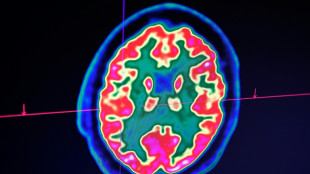

La pollution liée à 10% des cas de cancers en Europe, selon un rapport

Près de 10% des cancers en Europe sont liés à la pollution sous diverses formes, a averti mardi l'Agence européenne pour l'environnement (AEE), qui souligne que la majorité des cas sont évitables.